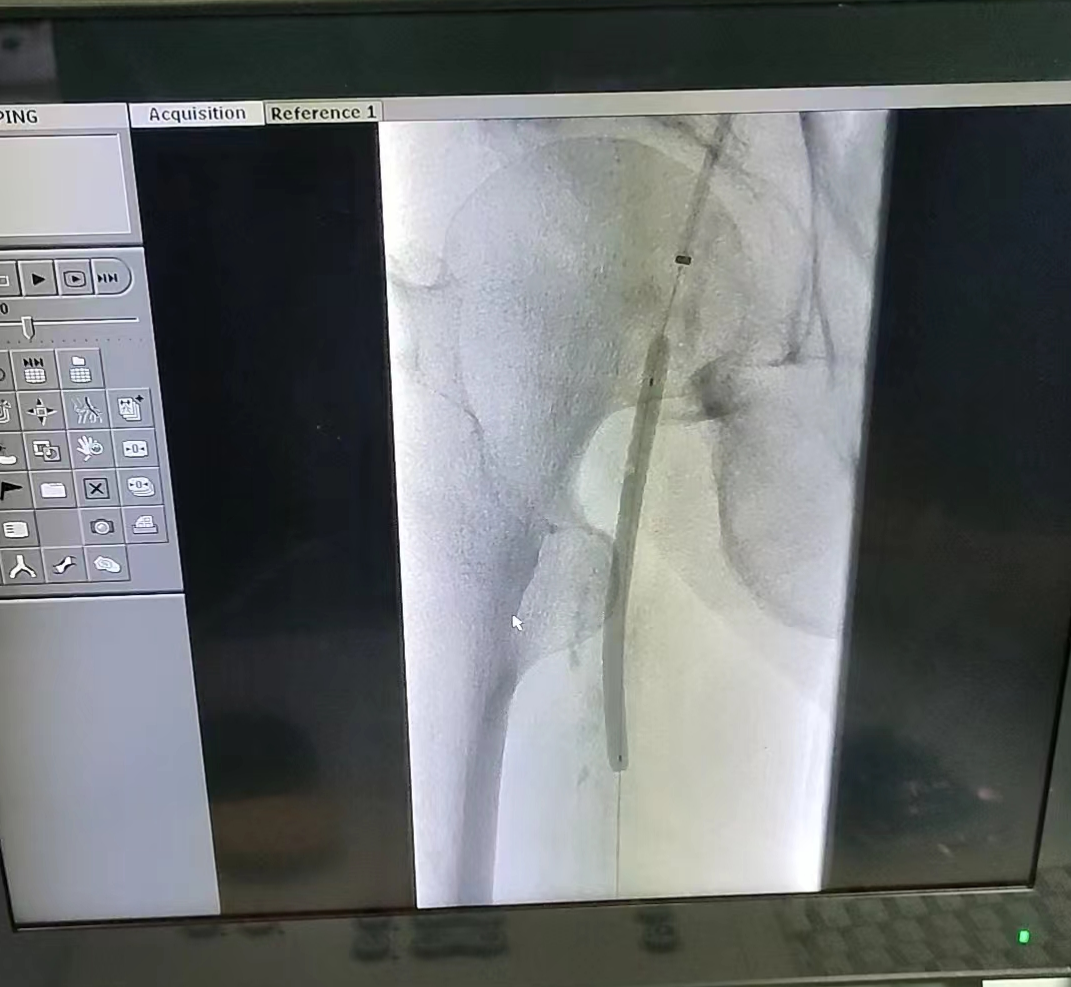

2024年1月3日,上海长征医院曲乐丰教授团队柏骏医生使用恒瑞医疗Cixpak™约束型外周球囊扩张导管成功开展一例下肢动脉硬化闭塞症(ASO)腔内血管重建术。这是恒瑞医疗Cixpak™约束型外周球囊扩张导管在国内的首次亮相。

该患者为老年男性,右下肢长段病变,术中柏医生运用逆穿开通技术建立输送通道,首先用普通球囊预扩,随后恒瑞Cixpak™约束型外周球囊扩张,最后使用药物球囊涂覆管腔,由于管腔准备良好,无限流性夹层的发生,没有植入支架,从而保证了管腔的远期通畅性。(具体病例细节我们随后发出)

在本次手术中,恒瑞Cixpak™球囊凭借优异的通过性,顺利达到目标位置,充盈后形态完好,扩张完成后管腔准备良好,无限流性夹层的发生,无需再植入支架,手术圆满完成。

达到工作压9atm后,形态保持良好!

术后球囊形态依然完好!